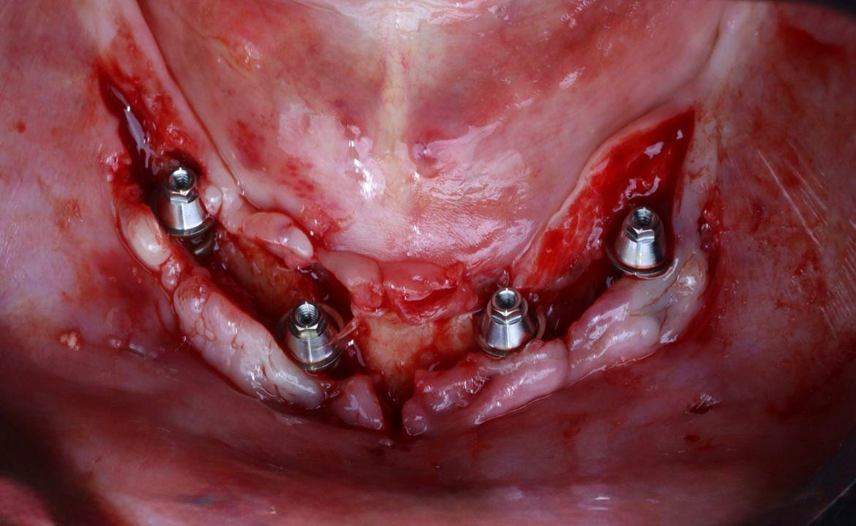

Paciente de 62 anos, do sexo feminino, sem comorbidades e história médica pregressa, apresentava severa reabsorção óssea em regiões anteriores e posteriores da mandíbula devido a uma peri-implantite (Figuras 1A e 1B). Feita a remoção dos implantes, a paciente optou por utilizar uma prótese total mucossuportada até a nova intervenção com prótese do tipo protocolo inferior. Após seis meses, a mandíbula encontrava-se cicatrizada (Figura 2). Como parte do protocolo diagnóstico, foi realizada tomografia computadorizada pela técnica do duplo DICOM. Com a severa perda óssea em região anterior de mandíbula, optamos por realizar a cirurgia de forma guiada, aumentando a previsibilidade e precisão da cirurgia. Os arquivos obtidos foram exportados para o software CoDiagnostiX, possibilitando a realização do planejamento reverso e o subsequente posicionamento virtual dos implantes (Figura 3). Com base no planejamento, optou-se pela instalação de quatro implantes Implacil Osstem CM AR Due Cone (3,5 x 7 mm), associados a mini-cônicos de 1,5 mm (Figuras 4A, 4B, 4C, 4D e 4E). A partir da tomografia da prótese da própria paciente, confeccionaram-se duas guias cirúrgicas: uma guia de pino de fixação (Figura 5) e uma guia de fresagem para a instalação dos implantes (Figura 6). Durante o procedimento cirúrgico, inicialmente foi posicionada a guia de pino de fixação para fresagem dos pinos de fixação e orientação da sequência cirúrgica (Figura 7). Após essa etapa, a guia foi substituída pela guia de fresagem dos implantes (Figura 8), utilizada para a fresagem e inserção dos implantes planejados (Figura 9). Concluída a instalação, optou-se por seguir o fluxo analógico, com a adaptação dos mini-cônicos 1.5 mm (Figura 10), realização da transferência de moldagem com silicona de adição leve e sutura com fio absorvível Vycril 6-0. O guia inicial foi adaptado com broca Maxicut, possibilitando sua utilização como molde de orientação para o laboratório protético (Figura 11). Após a moldagem, foram posicionadas as tampas de proteção sobre os implantes. Na fase protética, transcorridas 48 horas do procedimento cirúrgico, foi realizada a prova clínica da barra metálica e dos dentes (Figura 12). Na etapa subsequente, 72 horas após a cirurgia, procedeu-se à instalação e entrega do protocolo mandibular inferior e radiografia prévia, reabilitando funcional e esteticamente a paciente em curto espaço de tempo (Figuras 13A e 13B).